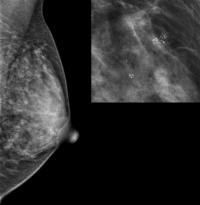

Which Benign Breast Disease Is Most Likely to Develop into Cancer? (IMAGE)

A radiological image of a suspicious finding. A biopsy would be needed to clarify if it is a benign breast disease and whether or not further investigation is needed.

Hospital del Mar Medical Research Institute, Barcelona, Spain